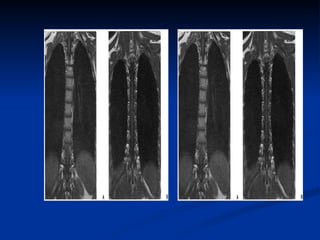

IRM dorsale  coupes  : une acquisition de repérage est réalisée dans un plan frontal  plans de coupe:  plan sagittal objectivant l'ensemble du rachis plan axial transverse pour une étude segmentaire épaisseur de coupe ne doit pas dépasser 3 à 4 mm dans le plan sagittal et 5 à 10 mm dans le plan axial

IRM dorsale Un examen IRM du rachis thoracique comprend le plus souvent : une séquence pondérée en T1, avec des coupes fines (3 à 4 mm) dans un plan sagittal  une séquence pondérée en T2 dans le plan sagittal ;  si besoin, des coupes axiales pondérées T1 ou T2 suivant l'indication.

IRM dorsale Unexamen IRM du rachis thoracique comprend le plus souvent : une séquence pondérée en T1, avec des coupes fines (3 à 4 mm) dans un plan sagittal une séquence pondérée en T2 dans le plan sagittal ; si besoin, des coupes axiales pondérées T1 ou T2 suivant l'indication.